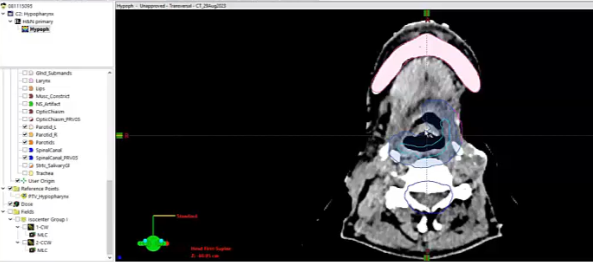

nasopharynx, MRI, PET, CT, NPX carcinoma, balloon procedure, right nasal pharyngeal carcinoma, 2A node, microscopic disease, T1, CLL, right parotid mass, squamous cell, right superficial parotidectomy, modified neck dissection, right temporal skin lesion excision, lymph node, ECE, bolus, dissecte...